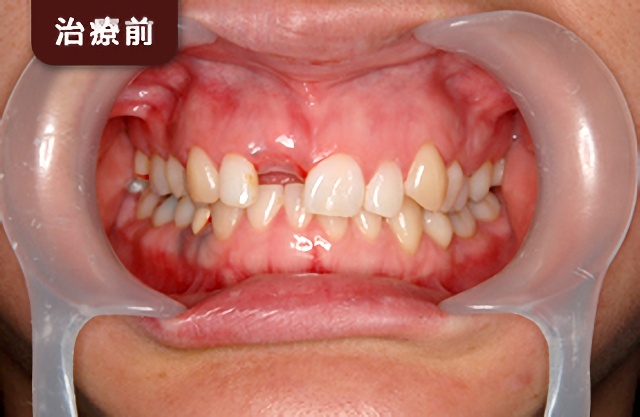

| 総入れ歯 | インプラント |

|---|---|

![]() | ![]() |

| 入れ歯が口の中で動いてしまい、「噛みづらい」や「話しづらい」などの不便さを感じることがあります。 | インプラントにより、入れ歯をしっかりと固定できるので、入れ歯を気にせず食事や会話を楽しむことができます。 |